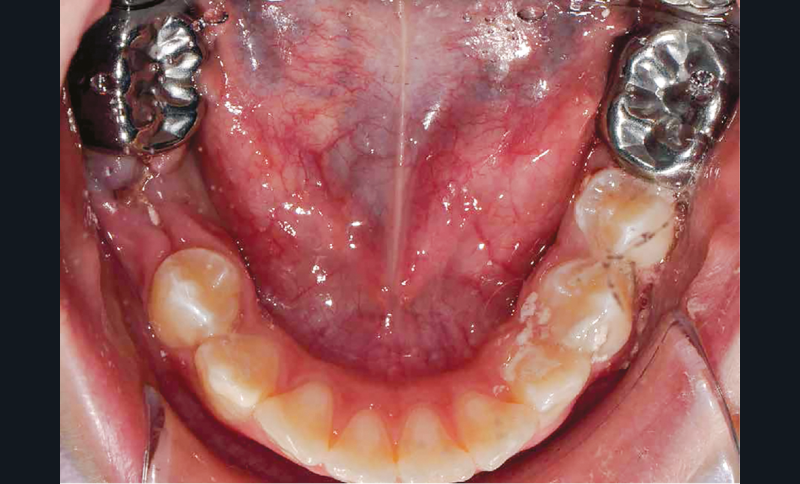

Afin d’optimiser les séances de soins, l’anesthésie intra-osseuse par injection électronique a été réalisée avec le Quicksleeper 5® dans les deux secteurs (fig. 3 et 4) afin de permettre la réalisation des coiffes préformées métalliques sur 36 et 46 dans la même séance (fig. 5 à 7). Il aurait été difficilement envisageable de réaliser les coiffes dans la même séance en utilisant une anesthésie tronculaire dans chaque secteur.

L’évolution de la médecine bucco-dentaire permet d’envisager des traitements efficaces. À l’heure actuelle, l’anesthésie ostéocentrale, notamment avec la réalisation d’injection assistée électroniquement grâce au Quicksleeper 5®, représente un outil incontournable (rapide, efficace, sécurisant) dans la prise en charge des patients en odontologie pédiatrique.